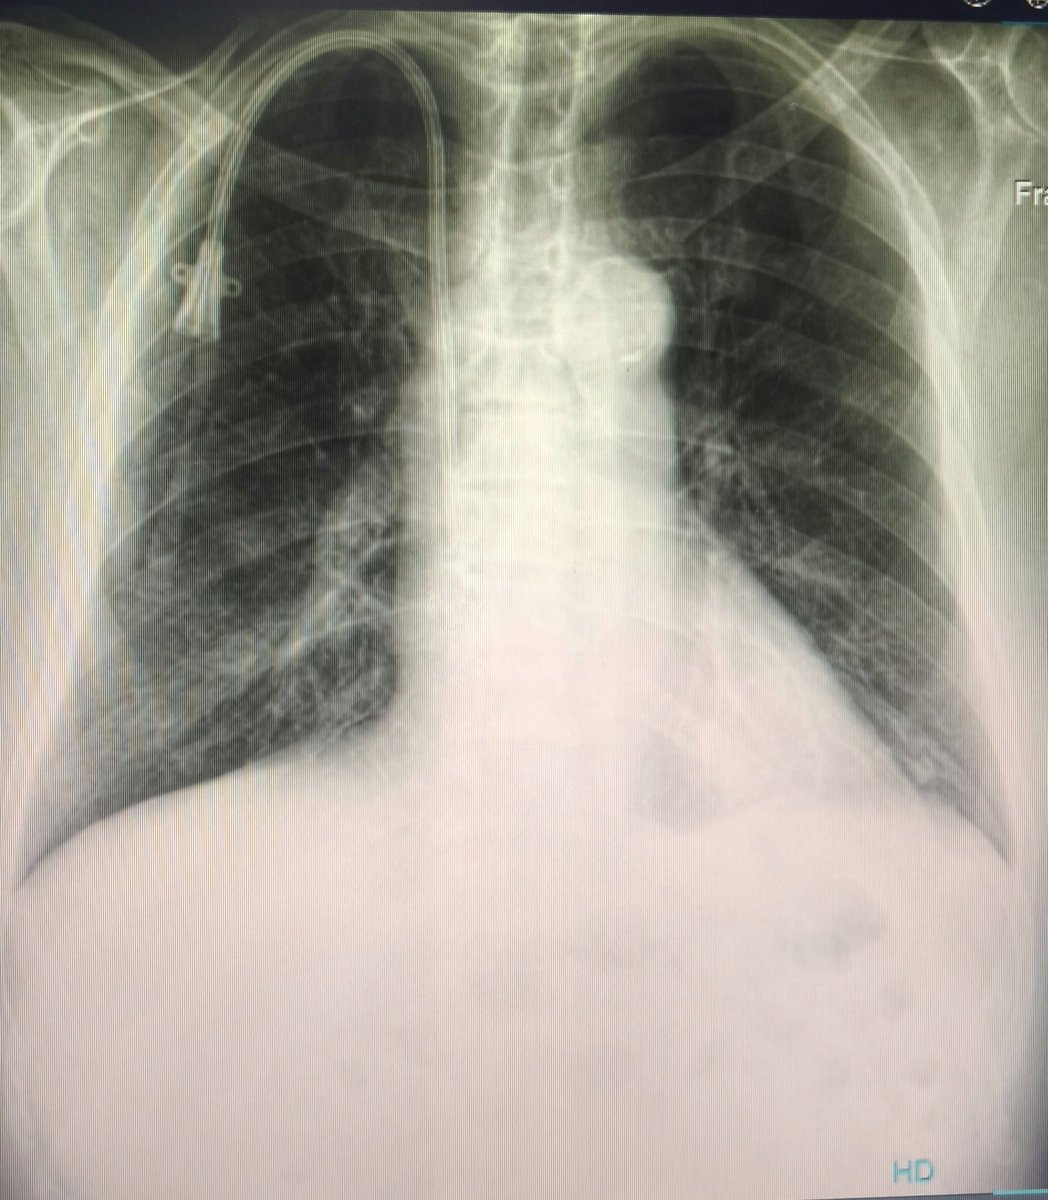

En tu perra vida verás una curva de catéter tunelizado más perfecta sptm 🔥🥵